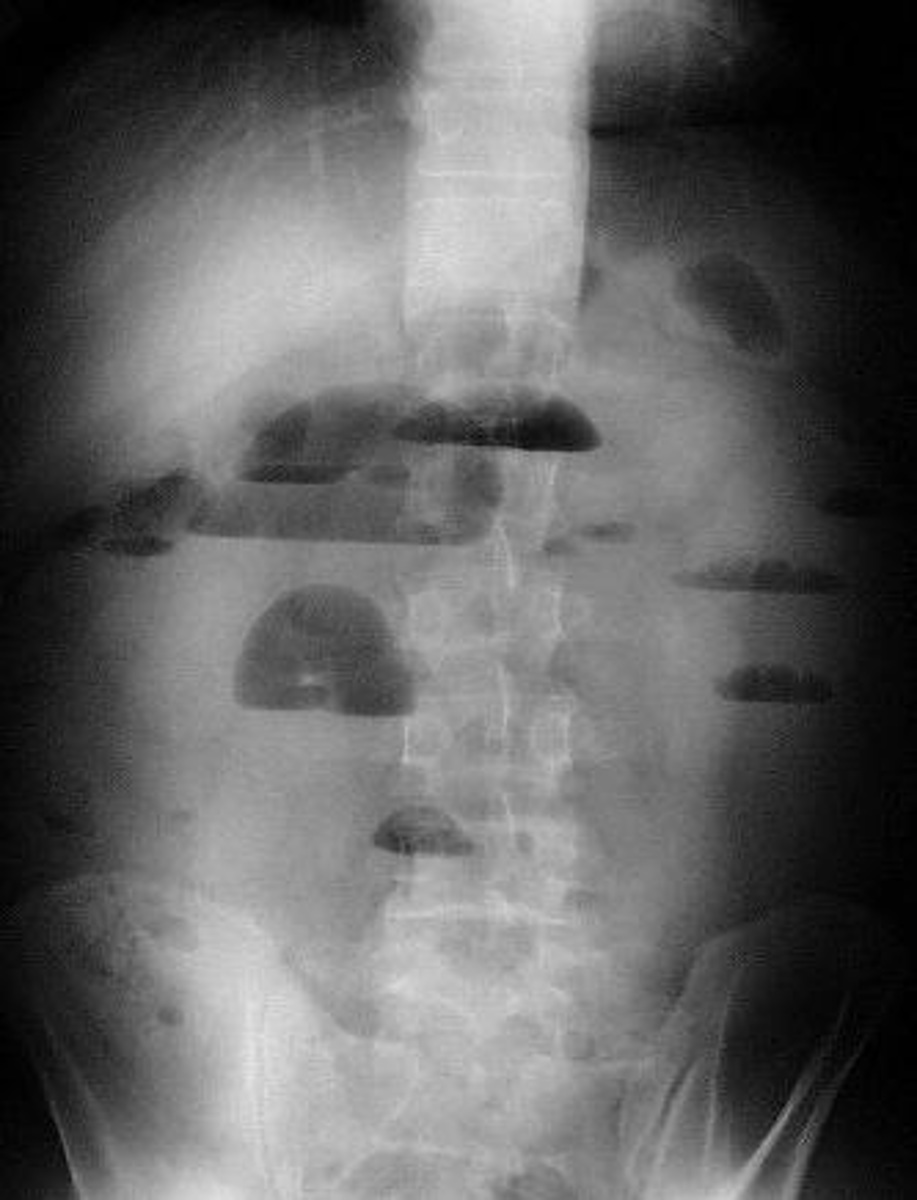

Иллюстрации и информация о симптомах острого кишечного непроходимости